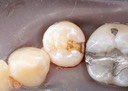

Joe Cha #18 pre-cementation

Joe Cha #18 finish